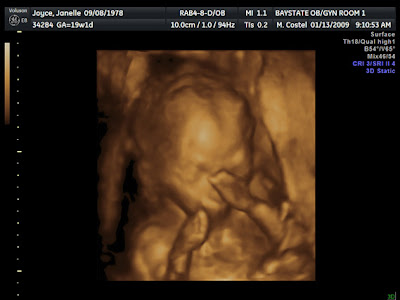

Mark and Janelle are having a boy! She had an ultrasound today and they asked if they wanted to know the sex. I guess at 19-20 weeks it becomes evident. They took many pictures and a couple of videos that you can see on my other blog:http://pamadeb.blogspot.com/